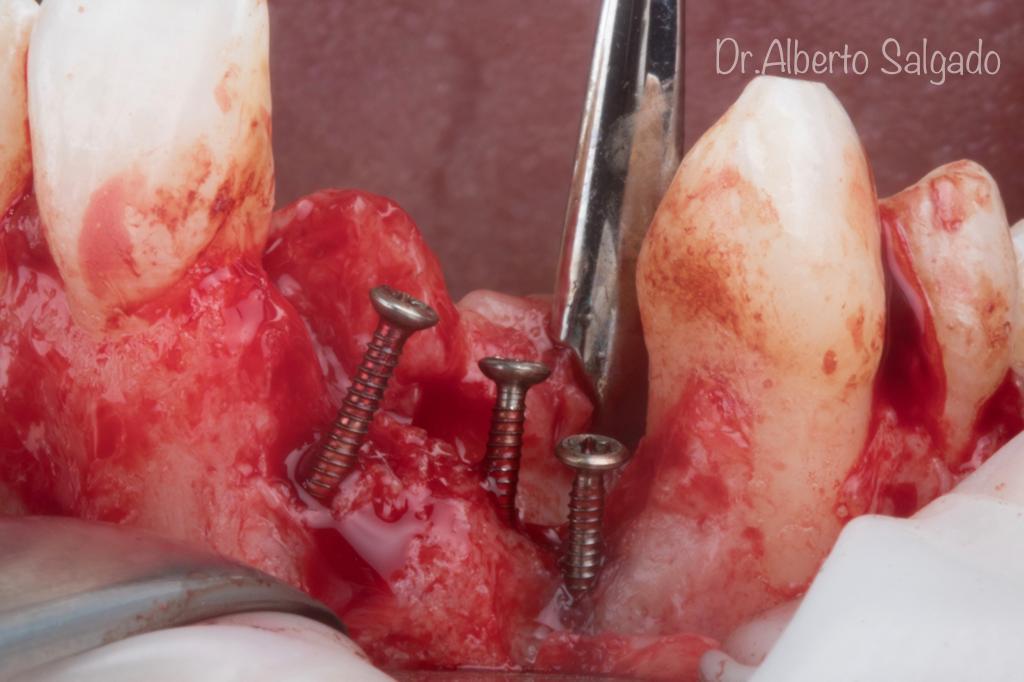

Dr. Alberto

Salgado